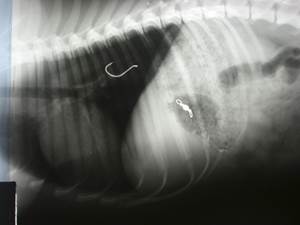

Для диагностики инородных тел в грудной части пищевода необходимо рентгенографическое исследование. Рентгенконтрастные предметы (кости, монеты) видно на обзорной рентгенографии, для визуализации рентгенпрозрачных инородных тел необходимо рентгенографическое исследование с контрастом.